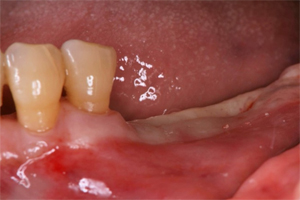

治療例1

やむを得ず抜歯後にインプラント治療をしたケースです。

銀歯の2本は残せないと判断

抜歯した歯